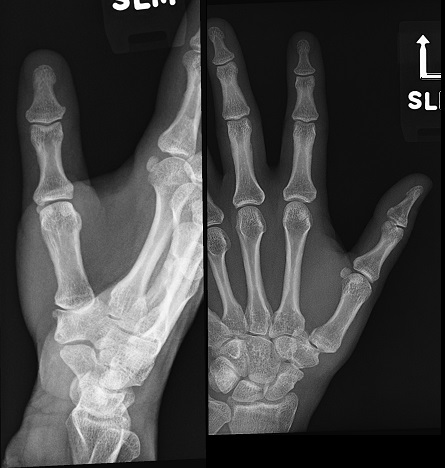

An 80 year old female presents to your office with a left ring finger deformity after a fall one week ago. She initially went to urgent care and xrays were unremarkable for a fracture (Figures 1 and 2). A photo of her left ring finger is shown in figure 3. On physical exam the left ring finger is in hyperextension at the PIP joint and flexion at the DIP joint. She able to flex her PIP joint with full motion. What is the best treatment option?